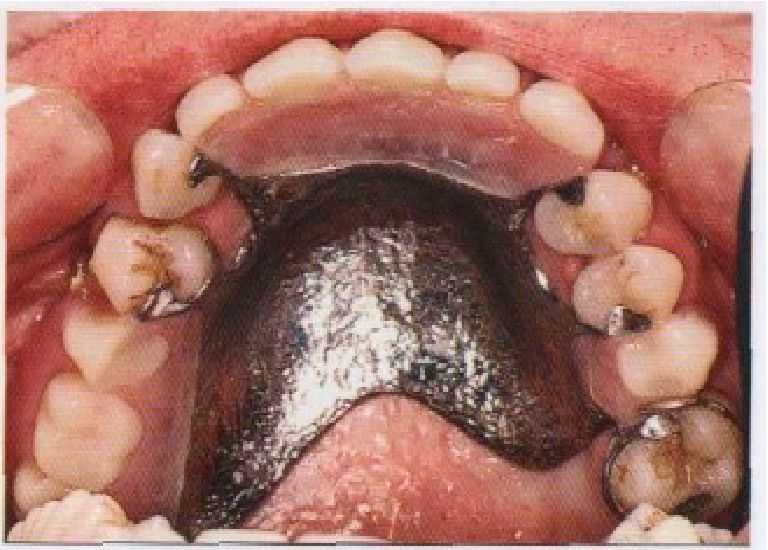

Рис. 3-3.

(а) Первый подкласс I класса по классификации Кеннеди,

(б) Первый подкласс II класса по классификации Кеннеди,

(в) Второй подкласс III класса по классификации Кеннеди,

(г) Четвертый класс по классификации Кеннеди.